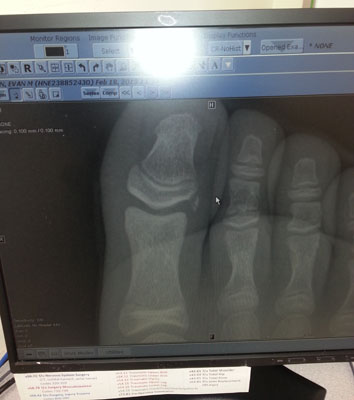

![]() It's just a little piece broken off. You can see it to the left of the mouse pointer. Evan broke is toe... |